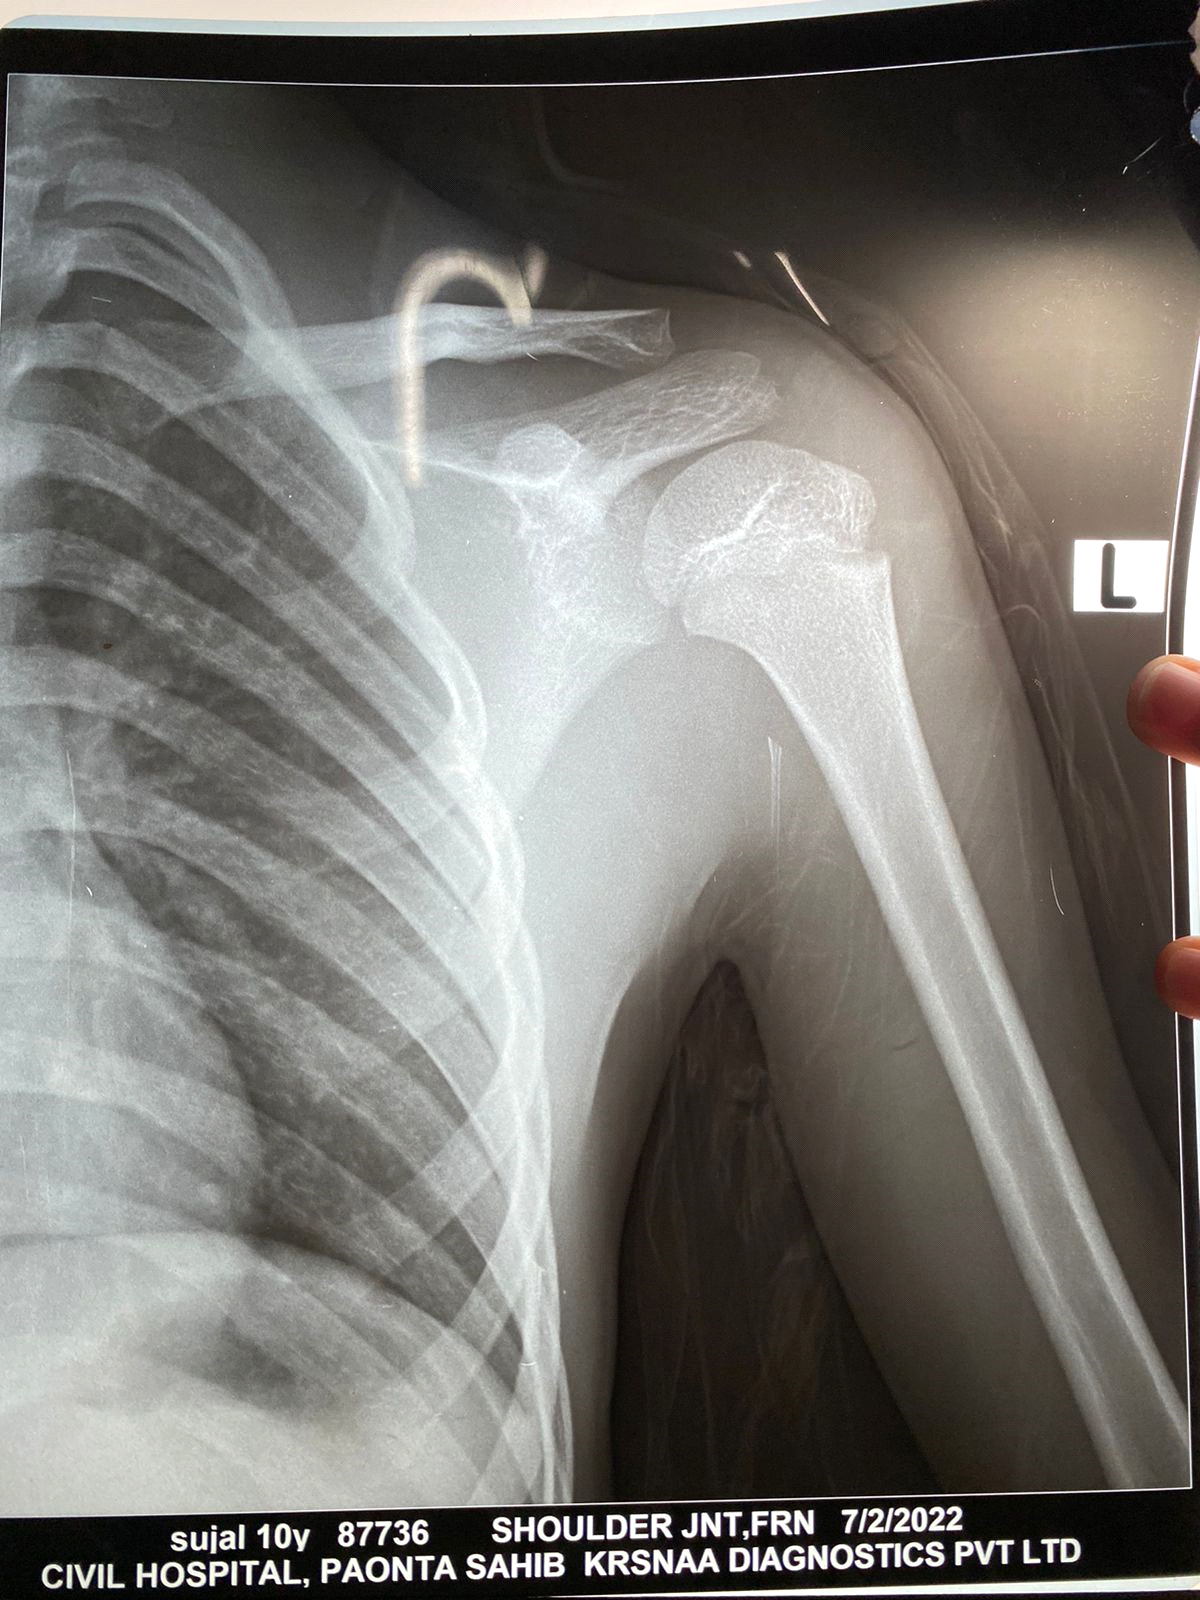

A 10-year-old male child presented to the emergency department with a history of pain and swelling in the left arm and left shoulder from 3 to 4 days. His mother gave a history of fall while playing 6 days back. He was afebrile with a blood pressure of 96/64 mm of Hg and Pulse rate 88/min. On examination, there was a nontender swelling in the left arm with decreased range of motion in the left shoulder joint. Distal pulses were normal, and there was not any neurological deficit. On the basis of history and examination, a clinical diagnosis of soft-tissue injury of shoulder or possibility of physeal injury of proximal humerus was made. He was advised rest, and shoulder immobilizer was applied, and oral analgesics were given. The patient was admitted and kept for observation. On Day 2 of admission, swelling was grossly increased with erythema and induration over whole of the left arm and shoulder (Fig. 1). X-ray image showed soft-tissue swelling of the left arm (Fig. 2). On palpation, the overlying skin was warm, and the patient had temperature of 100.1℉; however, vital signs were normal. WBC count was 11.24 × 103, Hb was 10 g/dL, and C-reactive protein reactive = 6.

Figure 2: X-ray showing soft-tissue swelling of the left arm.